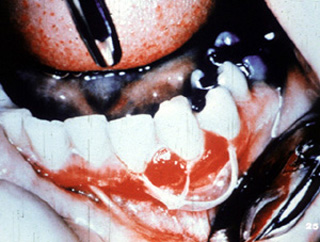

También pueden afectarse otras áreas del mucosa oral. Este señor presenta ulceraciones dolorosas de los mucosa bucal y labio. El examen clínico reveló  úlceras superficiales irregularmente formadas.

En otra vista, las lesiones están presentes en la mucosa yugal y la encía edentula.